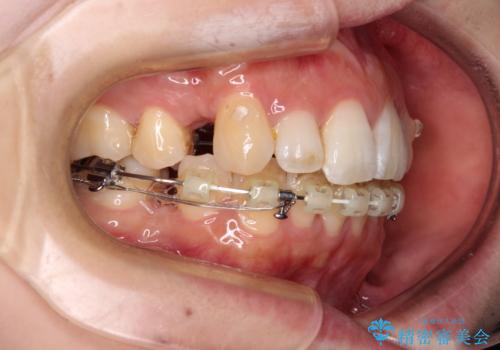

目立たない装置が希望であったため、上顎が裏側装置である、ハーフリンガル装置を選択されました。

第二小臼歯抜歯としたため、治療期間は長くなりましたが、満足のいく仕上がりとなりました。